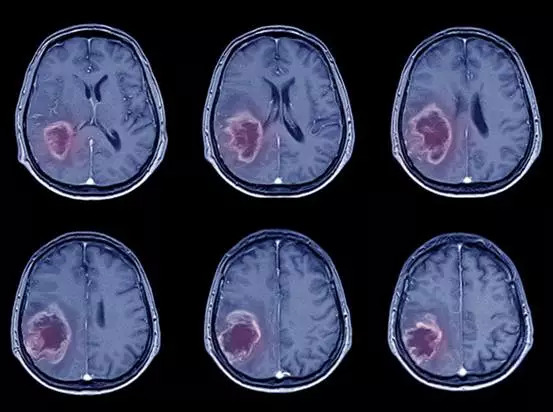

中风病患的脑部CT照片(来源:Freepik.com)